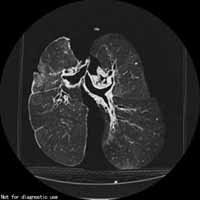

煤工塵肺2.X線檢查煤工塵肺胸片表現特徵有:網狀改變;結節狀改變;結節融合;塊狀陰影和多量絨毛狀改變。網狀改變被認為是煤工塵肺最早的表現,在肺野呈現瀰漫性細網狀陰影。而此時在臨床上無任何症狀。隨著結節的擴展,病變融合成不透明的進行性大塊纖維化,通常位於兩肺上野,也可跨肺葉融合至中、下肺野,有時僅發生在一側肺野,通常為大塊狀,均勻的、界限明顯的陰影。這些改變往往在單純性煤工塵肺彌散結節陰影的背景上發生。